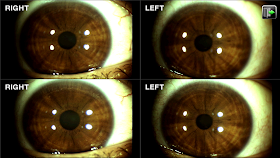

Los ojos son el espejo del alma

Dice el dicho popular: "Los ojos son el espejo del alma". Curiosamente hoy estuve en una cita de revisión donde el Oftalmólogo. He tenido hipermetropía y presbicia. Utilizo gafas con lentes formulados. Esta imagen que ven es la fotografía de mis ojos. Nunca los había detallado tan cerca. Mis ojos de color café son el espejo de mi alma. Aunque no tengo visión 20/20, me encantan mis ojos. Los ojos son muy delicados, debemos cuidarlos y no olvidar la visita al Oftalmólogo.